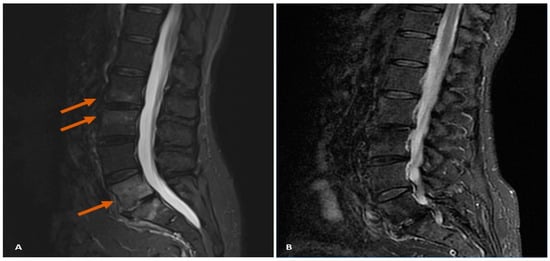

7.1. Case Study 1